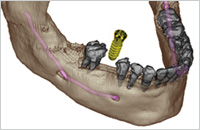

In besonderen Fällen nutzen wir die digitale Volumentomographie (DVT) bzw. die Computertomographie (CT), um mit dreidimensionalen Aufnahmen des knöchernen Gesichtsschädels schon vor einem Eingriff das Knochenangebot, die Knochenqualität und individuelle Besonderheiten zu erkennen. Mit den gestochen scharfen 3-D-Ansichten können wir die knöchernen Strukturen des Oberkiefers und des Unterkiefers, ausgesuchte, einzelne Segmente oder komplexe Zusammenhänge detailliert darstellen. Diese neue Technik eröffnet uns zuverlässige diagnostische und therapeutische Möglichkeiten in der Implantologie, Prothetik, Kieferorthopädie und Zahnerhaltung.